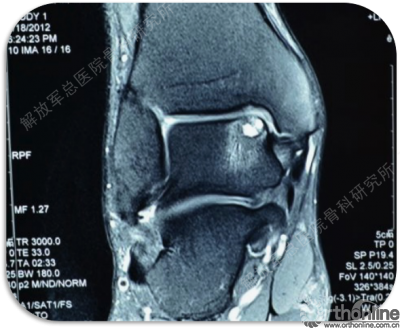

甄某,男,38岁,右侧距骨软骨损伤(运动伤)。

同样距骨软骨损伤完全可以利用第四代组织工程软骨进行修复,经过MRI检查可以诊断损伤部位,范围。此例患者软骨损伤存在软骨下骨板破坏及骨缺损。